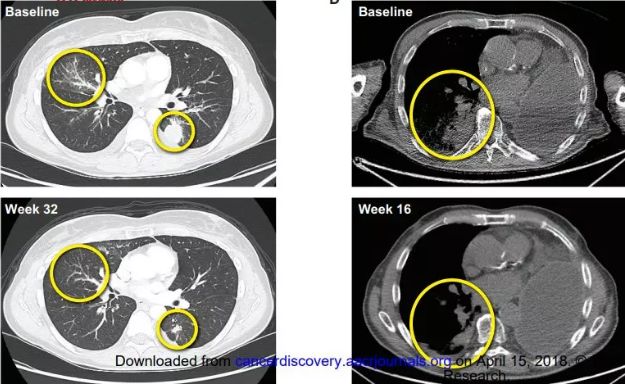

BLU-667是由Blueprint Medicines Corporation公司开发的一种高效且选择性的口服抑制剂,其靶向致癌RET-融合,抗性突变。该药物的临床前期和早期临床验证也已发表在Cancer Discovery上。

根据MD Anderson发布的新闻稿,BLU-667被选中进行调查是因为它对RET的选择性比其他激酶测试的选择性高100倍!并已被证明可有效阻止与多种激酶治疗抵抗有关的基因突变!

在开放性首次人类一期ARROW试验中,BLU-667表现出广泛的抗肿瘤活性,对于接受剂量≥60mg且具有至少1次基线后应答评估的RET改变患者,总体反应率(ORR)最高为37%(95%CI,20%-56%) (n = 30)。特别是非小细胞肺癌和MTC患者的ORR分别为50%和40%。在具有RET融合和突变的患者中,ORR为45%。详情点击:抗癌新药BLU-667在RET突变的晚期实体肿瘤中显示出广泛的临床益处!